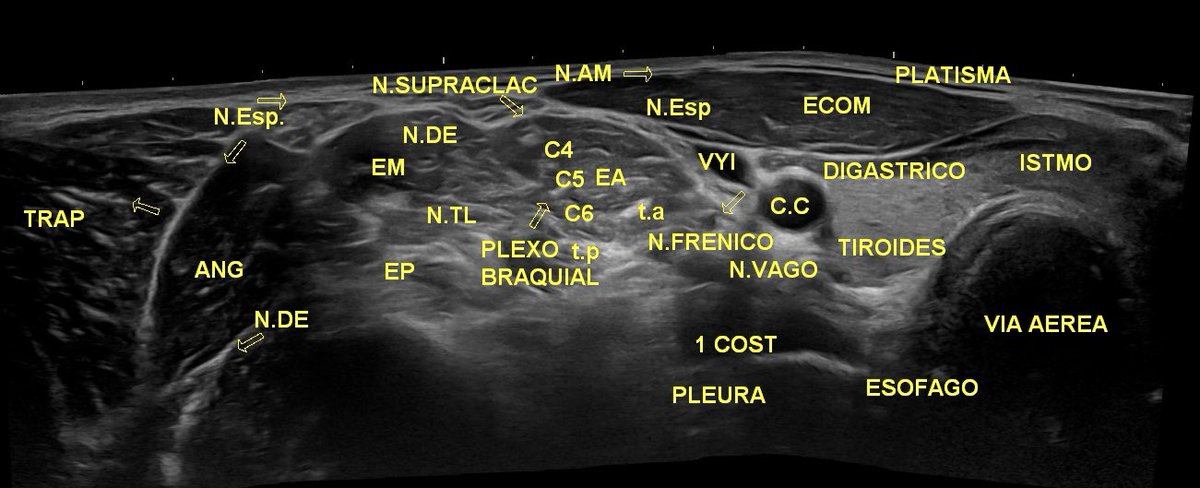

Curso de ecografía y neuromodulación en Sistema Nervioso Periférico ! 🌟 🗓 Fecha: 3 - 5 Octubre 📍 Ubicación: Madrid Impartido por: Grupo Muptherapy y Mariano Martin-Macho Martínez 👨🏫